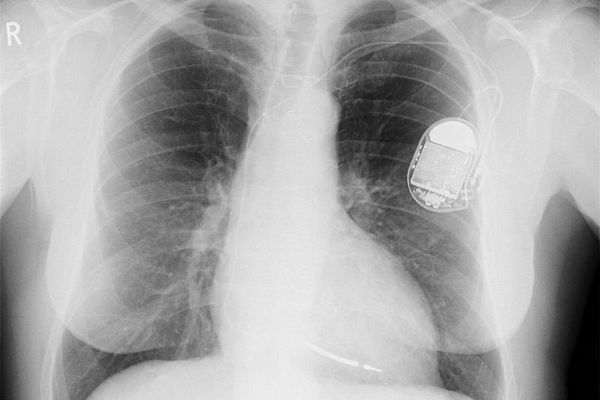

| Một lỗ hổng nghiêm trọng cho phép hacker điều khiển các thiết bị được cấy vào bên trong bệnh nhân. |

Máy khử rung tim cấy ghép là thiết bị nhỏ giúp ngăn ngừa các vấn đề về tim có thể gây tử vong bằng cách sử dụng các sốc điện nhỏ để điều trị nhịp tim không đều. Cơ quan này cho biết hôm thứ Năm rằng nếu lỗ hổng bị khai thác, chúng sẽ cho phép kẻ tấn công gây ra ảnh hưởng đến chức năng của các loại máy này.

DHS đã liệt kê hơn mười thiết bị tim Medtronic bị ảnh hưởng bởi các lỗ hổng. Bao gồm máy khử rung tim cấy ghép và máy khử rung tim điều trị đồng bộ hóa tim.